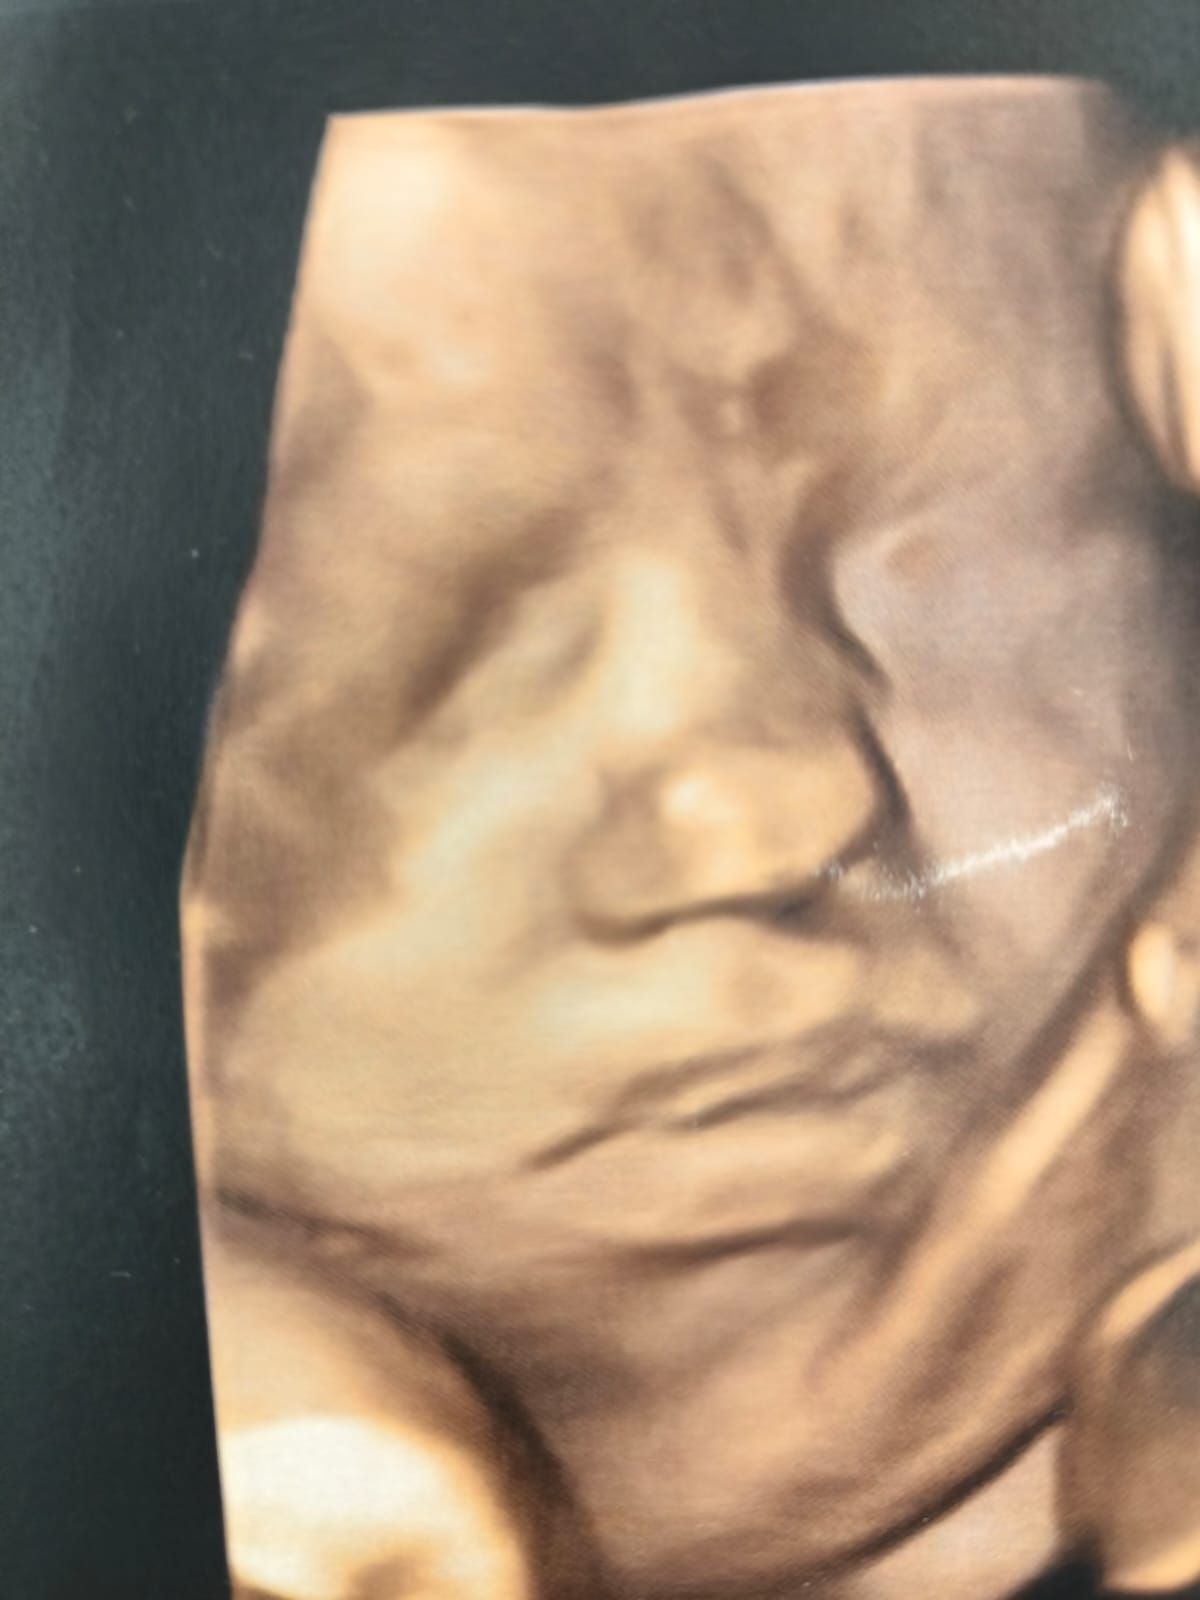

- Ecografie 3D e 4D;